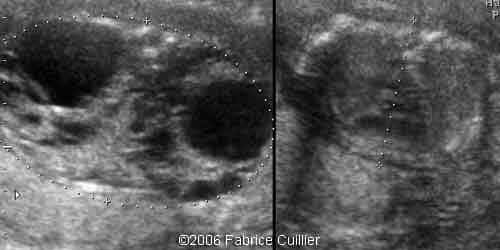

2D transverse view at 17 weeks showing bilateral hyperechoic kidney with no corticomedullary differentiation

1A.

1B.